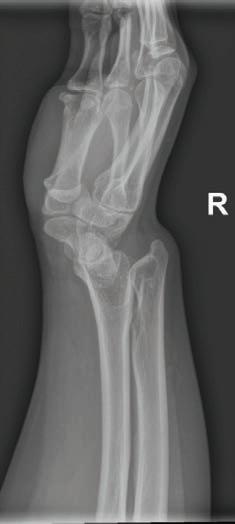

Enfermedad rara de la placa de crecimiento radial en un adulto joven que responde a terapias ‘Deformidad de Madelung’: Informe de caso.....................................................................37

Colaboradores: